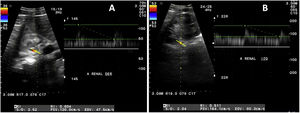

Ante la sospecha de hipertensión renovascular se procede a realizar Doppler (fig. 2) y como resultado se encuentra, en arteria renal derecha, una velocidad sistólica máxima de 120cm/s a nivel del ostium y 120cm/s a nivel de hilio, e índice de resistencia de 0,60. Por su parte, en la arteria renal izquierda se presenta una velocidad sistólica máxima de 137cm/s a nivel del ostium y 164cm/s a nivel del hilio, e índice de resistencia de 0,51. Estos valores normales no apoyan el diagnóstico de hipertensión renovascular, por lo cual, para descartar por completo esta posibilidad se realiza gammagrama renal 99mTc-DMSA con captopril, estudio basal riñón izquierdo 149,3ml/min, riñón derecho 79,9ml/min; estudio poscaptopril izquierdo 232,6ml/min y derecho 156,4ml/min.

Ultrasonido Doppler de arterias renales. A) Arteria renal derecha: velocidad sistólica máxima de 120cm/s a nivel del ostium y 120cm/s a nivel de hilio, índice de resistencia de 0,60. B) Arteria renal izquierda: velocidad sistólica máxima de 137cm/s a nivel del ostium y 164cm/s a nivel del hilio, índice de resistencia de 0,51.

El ultrasonido Doppler es un método económico, no invasivo, sin exposición a radiación ni medios de contraste; es una opción cuando no se dispone de otras herramientas para el diagnóstico y el seguimiento de AT. En el caso del paciente se utilizó para estudio de estenosis de arterias renales. El criterio mejor aceptado por diferentes estudios es una velocidad sistólica máxima por encima de 180cm/s, con una sensibilidad que puede llegar hasta el 90%9. Se realizó además gammagrama renal 99mTc-DMSA con captopril, el cual mostró incremento de tasa de filtrado glomerular posfármaco, siendo negativo para hipertensión renovascular. Este último estudio se recomienda para pacientes con baja probabilidad preprueba, con alto valor predictivo negativo en algunas series; en algunas de estas se reporta hasta el 100%10. Con base en estos datos, se descarta que el paciente presente este tipo de hipertensión.